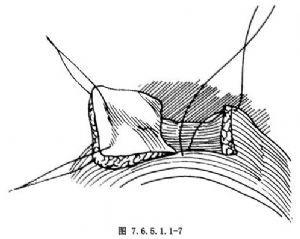

7.另一種方法是 切一橫向膀胱瓣,縫成螺旋管狀,與尿道吻合(Flocks和Boldas術,圖7.6.5.1.1-7,7.6.5.1.1-8)。